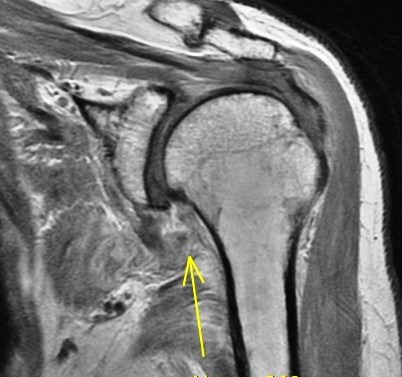

75 y/o s/p dislocation

Dislocation pathology is typically different in older patients than younger patients. The great majority of first time dislocators under the age of 40 suffer a bankart lesion (avulsion of the labral ligamentous complex on the glenoid side). Older folks often suffer a rotator cuff tear including the supraspinatus or subscapularis (or both). This patient had an SST tear but in addition also has a HAGL lesion (humeral avulsion of the glenohumeral (IGHL) ligament). She also has subscapularis partial tearing associated with a near complete dislocation of the biceps (findings that I think were preexisting). Reference article.

HAGL lesion and rotator cuff tears